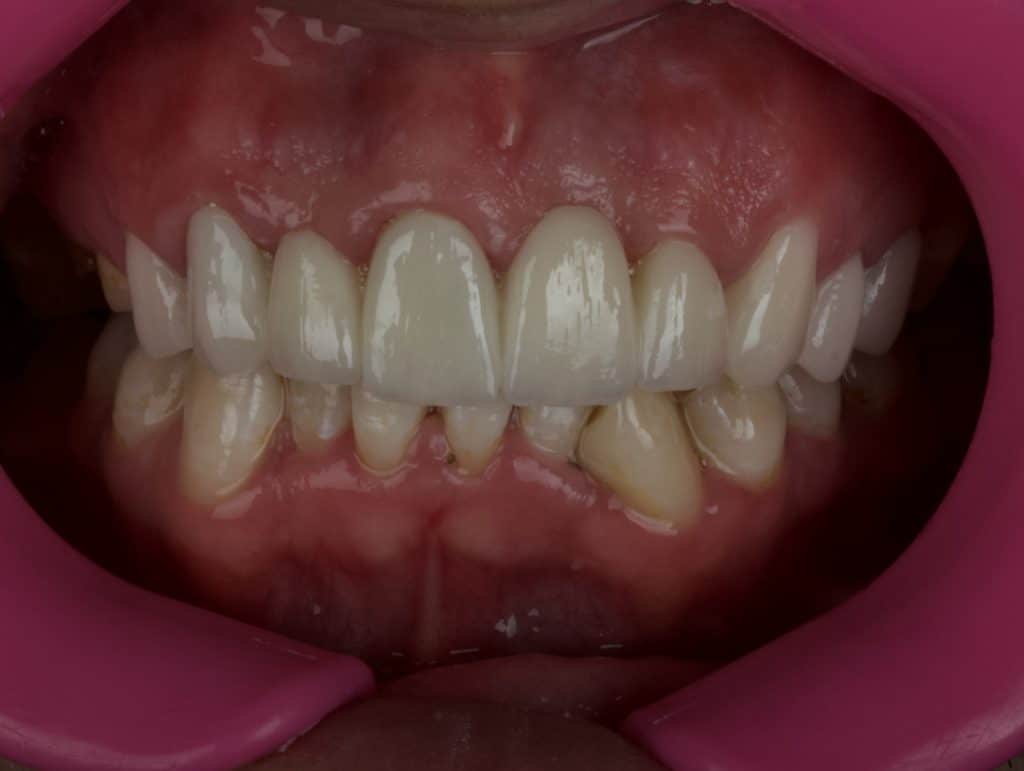

Immediately after cementation

Old restoration vs new restoration